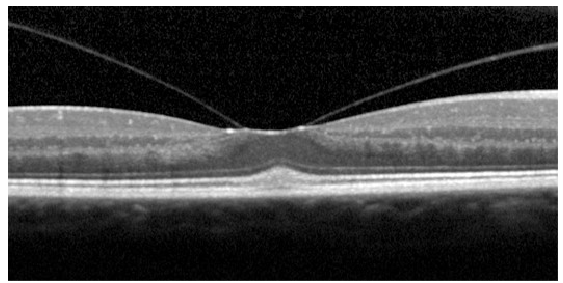

Name the condition

Retinal detachment and holes

Vitro-macular traction Note: while this looks very serious, this is only “traction” and does not warrant referral.

The patient is most likely not aware of it

Vitreous has come off on either side of the macula but it’s pulling the macula up, only classed as traction- wouldn’t refer at this point, not much effect on VA